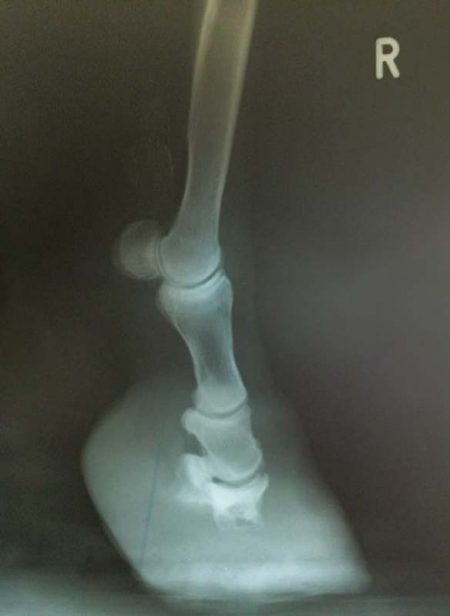

Das Röntgen von Moritz‘ Hufen hat erschreckende Befunde zu Tage gebracht. ![]()

Sein Hufbein ist in beiden Vorderhufen komplett aufgelöst, zerstört. Die jahrelang unbehandelte Hufrehe und die dadurch bedingten Entzündungen haben die Hufbeine komplett zerfressen und nichts mehr übrig gelassen. Es ist verwunderlich, dass die Hufkapsel überhaupt noch hält.

Bis es zu solch gravierenden Auflösungserscheinungen kommt, vergehen Jahre – und diese müssen von unerträglichen Schmerzen geprägt gewesen sein.